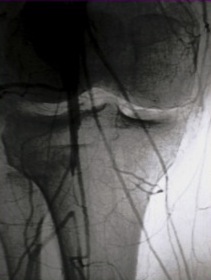

Normal angiogram

Popliteal artery injury on angiogram

Disadvantages

- technically demanding

- potentially less accurate than CTA

- operator dependant

Technique

- open approach to proximal femoral artery

- place catheter in artery with 3 way tap

- 20mls Omnipaque / water soluble dye

- fluoroscopy over distal femur

- repeat for proximal tibia

- must show films to radiologist for interpretation of subtle signs

Rose et al. American J Roengenology 1987

- angiography 98% sensitive and specific for major arterial injury

- 16% technically compromised